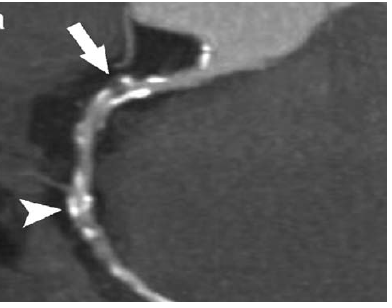

💓 心脏成像的挑战

心脏是一个不停跳动的器官,传统CT很难获得清晰的心脏图像。64排及以上的MSCT具有足够高的时间分辨率(~100ms),可以在心脏舒张期的短暂"静止"时刻完成扫描,从而获得清晰的冠状动脉图像。这使得CT冠状动脉造影(CTCA)成为一种无创的心脏检查方法。

CT血管造影(CTA)图像,通过注射造影剂并利用多排螺旋CT快速扫描,可以清晰显示血管结构